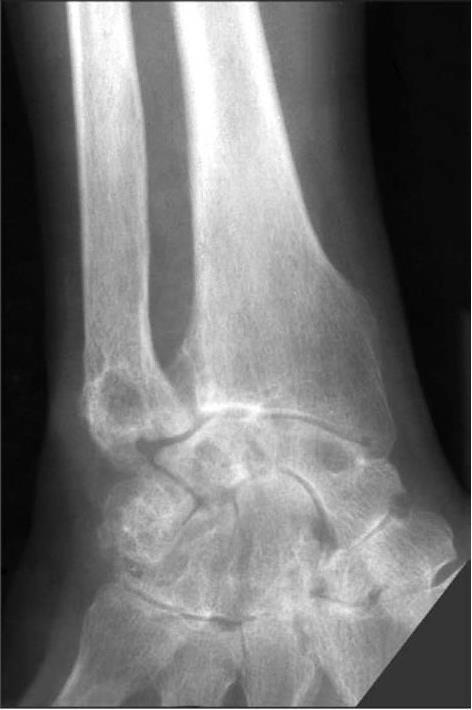

Множественные и крупные подагрические узелки наблюдают при резко выраженной гиперурикемии. Однако абсолютным признаком подагры может быть только выявление кристаллов мочевой кислоты. Кристаллы МУН (моноурата натрия) обнаруживают уже после первого эпизода артрита. Кристаллы МУН определяют в синовиальной жидкости даже вне приступа. Кристаллы уратов имеют вид палочек или тонких игл с обломанными или закругленными концами длиной около 10 мкм. Микрокристаллы уратов в синовиальной жидкости обнаруживают как свободно лежащими, так и в нейтрофилах. Рентгенологически вблизи тофусов выявляют округлую деструкцию костной ткани, обусловленную лизисом кости вокруг отложения кристаллов уратов (рис. 24, 25). Последние обычно рентгенонегативны, но иногда рядом можно выявить отложение солей кальция.

Округлую костную деструкцию называют «штампованными дефектами», симптомом «пробойника». Деструкция обычно расположена субкортикально, как в эпифизах (субхондрально), так и на границе эпифиза и диафиза, а также может быть локализована вне сустава, в диафизах, с участками костной резорбции вокруг. При расположении уратов вблизи полости сустава из-за гибели хряща можно наблюдать сужение суставной щели. Как результат прорыва конгломерата уратов в полость сустава из кости может быть обнаружена краевая деструкция костной пластинки, но это наблюдают, как правило, на фоне других округлых очагов деструкции костной ткани — «пробойников». Рядом с отложением уратов можно видеть гипертрофическую костную реакцию. При значительной гибели суставного хряща подагра осложняется вторичным остеоартрозом с появлением краевых костных разрастаний — остеофитов.

Рис. 25. Рентгенограмма левой стопы больного подагрой